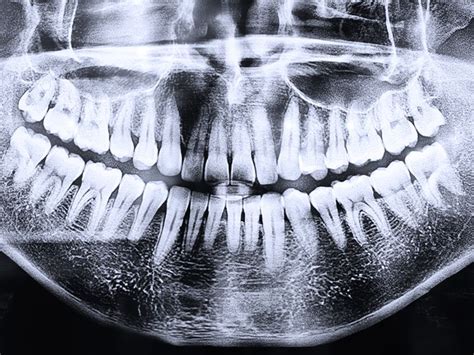

La ortopantomografía, también conocida como radiografía panorámica dental, es una técnica de imagen que captura una visión completa de la boca, incluyendo todos los dientes, la mandíbula y las estructuras circundantes. Es una herramienta esencial para el diagnóstico y la prevención de problemas dentales.

La radiografía panorámica es una técnica radiológica que muestra las estructuras óseas (los maxilares, la articulación de la mandíbula y los dientes) del rostro del paciente en una sola imagen general. Para ello, se vale de una máquina de rayos X especial, que rota alrededor de la cabeza del paciente.

Con un mero golpe de vista, un odontólogo experimentado puede detectar problemas que no habría podido identificar con un mero examen visual. Además de para el odontólogo general, la información contenida en una de estas ortopantomografías es muy valiosa para los profesionales de ramas odontológicas como la cirugía oral, la implantología, la ortodoncia o la periodoncia.